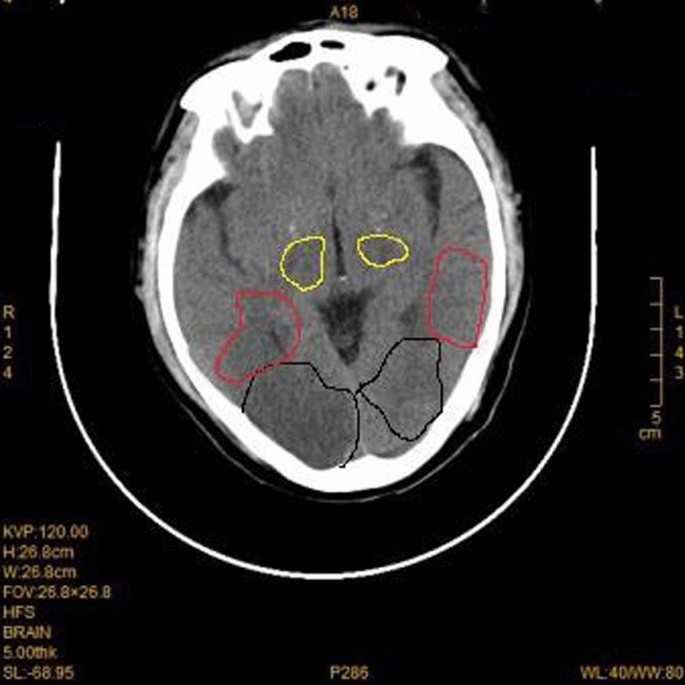

General anesthesia was induced and maintained according to standard protocols during surgical preparation. Then right pneumonectomy was performed, and the surgical incision was located at the posterolateral side of the fourth intercostal space. The pulmonary artery, pulmonary vein and bronchus were cut off with a stapler, with intraoperative bleeding of about 100 ml. After the operation, the thoracic drainage tube was clamped, and the patient returned to the ward after waking up. Three hours after the operation was completed, the patient suddenly lost consciousness while sitting in bed chatting with his wife. The patient’s blood pressure was low (76/53 mmHg), and the indexes of heart rate, respiration and oxygen saturation were normal. After opening the thoracic drainage tube, a small amount of tension gas and 200 ml of bloody fluid was discharged. We immediately performed CT examination and excluded brain lesions. CT examination showed that there was a large amount of gas in the tissue space between the chest and neck (Fig. 2). Blood clots accumulated in the thoracic cavity, and CT angiography showed no abnormalities in the major cerebral arteries (Fig. 3). However, multiple free air can be seen in the blood vessels of bilateral frontal sulcus (Fig. 4). In addition to free air, suspicious cerebral infarction was also seen in the right occipital lobe (Fig. 5). It is presumed that air entering the cerebral circulation led to air embolism. The patient had seizures soon after the CT scan, manifesting as binocular gaze and tremor of limbs. Then the patient was quickly transferred to ICU. Respiratory assistance, mannitol dehydration and empiric antibiotic treatment were used after ICU transfer. 800 ml pleural fluid was drained from the thoracic cavity 6 h after the operation, and a second thoracotomy was performed to stop bleeding. Then blood clot was removed from the thoracic cavity. After the operation, the patient was sent back to the ICU for ventilator-assisted breathing, and the head was protected by mild hypothermia using an ice blanket to prevent excessive brain damage. At the same time, mannitol dehydration was used to reduce brain edema and anti-infection treatment was carried out. On the next day, the brain CT showed a significant decrease of air in the brain (Fig. 6). There was no significant increase in cerebral infarction lesions compared with the first day. After 3 days of ventilator-assisted breathing, the patient’s condition gradually improved. On the third day after air embolism, the brain CT was reexamined. There were patchy low density areas in bilateral thalamic basal ganglia, temporal lobe and occipital lobe, which was cerebral infarction lesions. The patient was discharged after 25 days of treatment after cerebral infarction. He was conscious at the time of discharge, with neurological impairment symptoms of bilateral in which symptoms of left limb are more serious. The process from onset to recovery was smooth. After 3 months of follow-up, most of the neurological deficit symptoms had been recovered except for the left upper limb (Fig. 7).